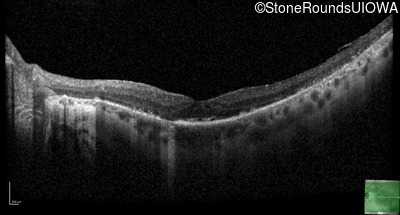

Optical Coherence Tomography - Left - 20/20 -2

Exemplar / OCT Stack

OCT Stack